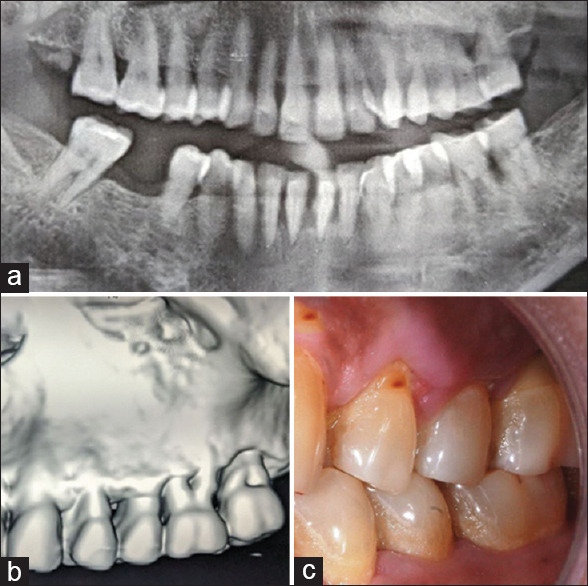

Materials and methods: Thirteen patients were recruited for this split-mouth study, each presenting with a hopeless molar in one quadrant and a partially edentulous ridge with a missing molar in the contralateral quadrant. The compromised molars were atraumatically extracted without flap reflection, followed by immediate placement of ultrawide diameter implants. In the opposing quadrant, missing molar sites were rehabilitated with standard-diameter implants. Crestal bone remodeling, implant stability, and soft-tissue maturation were evaluated 1-year postloading. Radiographic assessments and Osstell device measurements were performed at implant placement, 3 months postrestoration, and 1 year after prosthetic function.

Results: The findings suggest that immediate flapless molar extraction helps preserve vascular integrity, and ultrawide diameter implants may serve as a viable treatment modality for molar replacement. The wider implant surface effectively dissipated occlusal forces, and bone dimensions were well maintained in terms of both width and length. Soft-tissue maturation, including attached gingiva thickness, was favorable after 1 year of prosthetic function. Healed partially edentulous ridges restored with standard-diameter implants also demonstrated stable functional outcomes at the 1-year follow-up. However, a notable limitation of this approach was the inadequate bone volume to accommodate the width of the missing molar crown, leading to occlusal and maintenance challenges. In addition, incomplete papillary fill around implant-supported restorations was observed due to reduced bony dimensions.